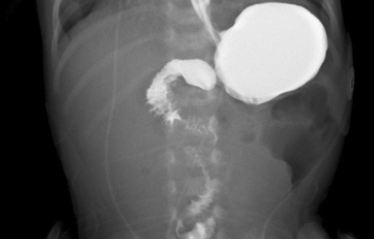

How is duodenal atresia diagnosed?

Abdominal x-ray showing double bubble sign, contrast studies may confirm the diagnosis